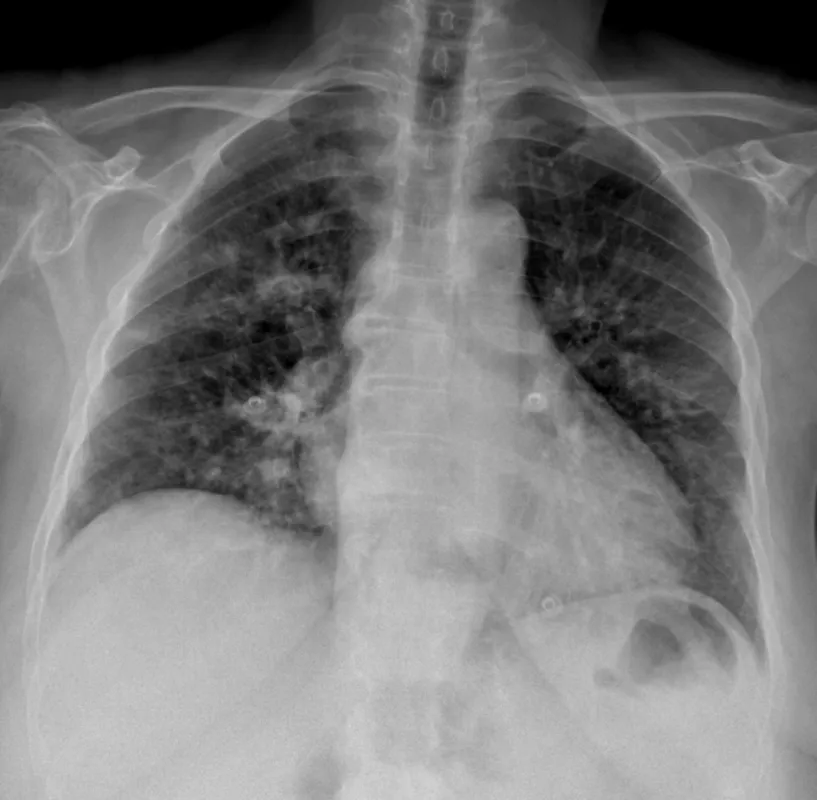

– Fejlesztettünk egy szoftvert, ami lefuttat egy digitális formában elkészült mellkasi röntgenfelvételen egy mesterséges intelligencia alapú elemző algoritmust, és így kapjuk meg az eredményt, hogy egészséges-e a tüdő vagy beteg. A rendszer „pontonként letapogatja” a tüdőt, olyan, mintha sok orvos végignézné a képet, és mindegyik csak egy-egy elváltozást keresne. Fontos hangsúlyozni, hogy a szoftver nem dönt az orvos helyett, csak segít neki a döntésben.

Jelenleg gyorsteszttel vagy laboratóriumi eljárással mutatják ki a koronavírust, de ezt előszűrhetné a röntgen vagy akár a CT, és ezek a berendezések ott vannak az egészségügyi intézményekben. A rendszert be tudnák tanítani CT felvételek elemzésére is, ehhez csak kellő számú felvételre lenne szükségük.